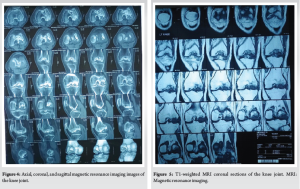

Magnetic resonance imaging (MRI) scan of the knee (Figs. 3, 4, 5) was done which revealed large serpiginous areas of lowsignal intensity on T1W images with double line sign and rim sign on T2W images involving whole of lateral femoral condyle and trochlear surface, subchondral bone collapse and bone marrow edema in lateral femoral condyle, trochlear surface and also part of the medial femoral condyle. Mild joint effusion, along with osteoarthritic changes, was noted.

Considering the findings present in the MRI and X-rays, which revealed involvement of the trochlear surface and medial compartment which was although minimal, the option of performing UKA (unicondylar knee arthroplasty) on the lateral condyle seemed questionable. Hence, after thorough discussion with the patient, and keeping in mind the patient’s demands and expectations, TKA with robotic assistance was planned and executed. 3D computed tomography (CT) of the knee with the limb obtained as per Cuvis Robotic system guidelines, and planning for the TKA was done using Cuvis J planner software. The CT scan confirmed and correlated well with the findings of the MRI and X-rays.